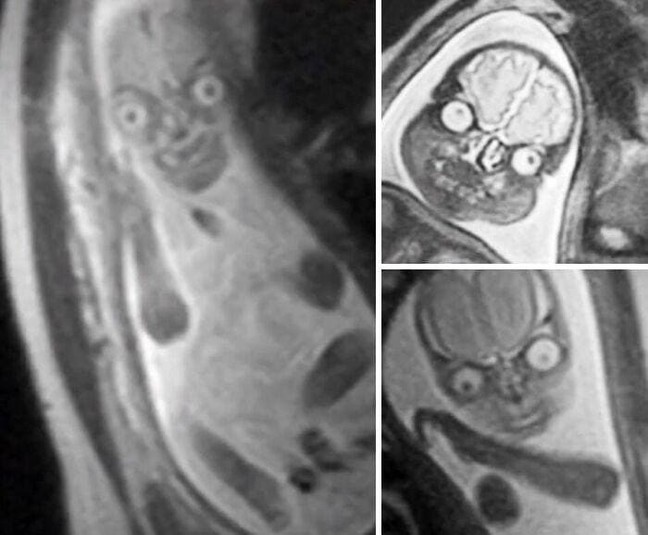

Фото обычных вещей в странных ракурсах, способных напугать до потери сознания

Под воздействием ракурса или перспективы даже самые обычные животные или растения могут казаться чем-то другим: непонятным и пугающим.

Снимки безобидных предметов из этой подборки, словно вещи на стуле, которые в час ночи резко стали напоминать силуэт незнакомца, способны любого человека напугать до потери сознания.

«Снеговик, о создании которого я пожалел ближе к ночи», «Свадьба во времена карантина. Выглядит пугающе, если не знать контекста», «Картофель, о котором забыли на пару месяцев», «Краб-отшельник использует выброшенную кукольную голову в качестве раковины», «Медведь, который выглядит так, словно это человек в костюме медведя», - комментируют фото пользователи сети.